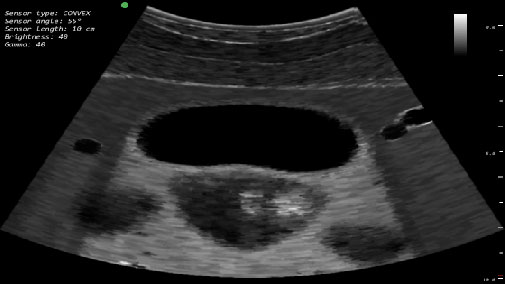

Виртуальный симулятор ультразвуковых исследований (УЗИ) SonoVision – обучающий тренажер на единой платформе обеспечивающий освоение основных навыков проведения ультразвукового исследования, понимание и идентификацию различных заболеваний и патологии внутренних органов человека.

SonoVision – симулятор ультразвуковой диагностики является инструментом для профессионального изучения медицины. Это виртуальный симулятор для отработки навыков ультразвуковой диагностики. Он используется как студентами, так и практикующими специалистами в клиниках и больницах. Симулятор ультразвуковой диагностики – прекрасное дополнение к традиционному обучению и повышению квалификации медицинского персонала.

Новое поколения симулятора УЗИ гарантирует высочайший уровень детализации внутренних органов, а работа с анатомически корректным манекеном обеспечивает реалистичные тактильные ощущения и визуальную картину при выполнении вмешательств. В симуляторе реализовано более 40 клинических сценариев.

Высочайший уровень детализации внутренних органов. реалистичные тактильные ощущения:

- Трехмерная модель органов в окне виртуальной реальности;

- Отслеживание положения датчика УЗИ в режиме реального времени;

- Измерения органов и настройка параметров УЗИ изображения.